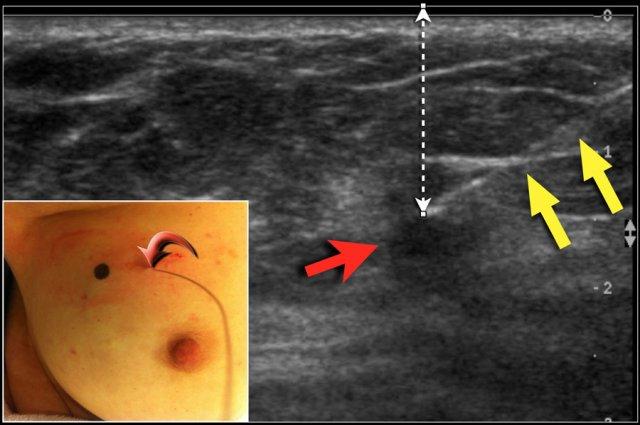

Định vị bằng dây kim loại

DCIS và nhiều khối u nhỏ không thể sờ thấy được. Trong những trường hợp này, bác sĩ chẩn đoán hình ảnh đặt một dây kim loại có móc vào vùng cần được cắt bỏ.

Dây kim loại được đặt vào trong khối u hoặc vùng DCIS, dưới hướng dẫn của siêu âm hoặc định vị lập thể.

Với siêu âm, vị trí của khối u được đánh dấu trên da trong khi bệnh nhân giữ tay ở cùng tư thế như trong lúc phẫu thuật. Độ sâu chính xác của khối u dưới da cũng được ghi nhận.

Hình ảnh cho thấy đường đi của dây kim loại (mũi tên vàng) hướng tới khối u (mũi tên đỏ). Lưu ý chấm đen trên da để đánh dấu vị trí chính xác của khối u.

Mũi tên cong chỉ điểm dây kim loại đi vào vú.